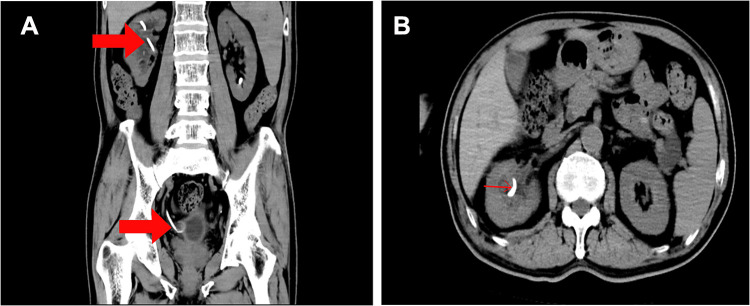

Figure 4.

(A) In the CT window, the red arrows point to the DJ tubes placed in the kidneys and bladder (B) in different slices of the CT window, the DJ tube of the kidney is indicated by the red arrow.